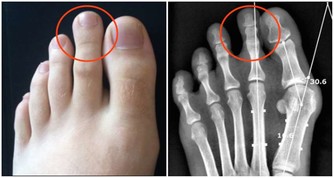

4、骨骼強壯:中醫認為,腎主骨,骨靠腎精滋養,腎好骨才好。腎氣衰敗會出現骨質疏鬆、腰酸背痛,甚至牙齒出現鬆動。